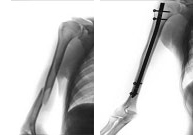

Fractures at this level are rare (5%) and follow a high-energy impact. Contact sports such as martial arts and sports that can produce violent falls (downhill skiing, motorcycling, cycling, canyoneering, paragliding) are predisposed to this type of fracture. The usual treatment is non-operative. Minimal intervention introducing an intramedulary nail is sometimes required to stabilized the fragments so that the patient can resume his normal activities as soon as possible.